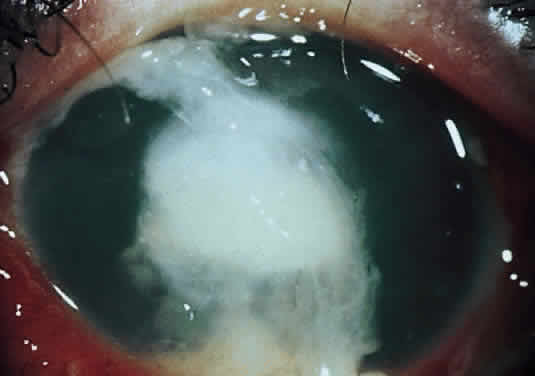

Clinically, the infected staphylococcal corneal ulcer presents with a yellow-white, well-demarcated area of infiltrate, which appears directly beneath an epithelial defect (Fig. 2). On occasion, multiple, small satellite lesions may develop. The infection may initially be superficial; however, if inadequately treated it can produce a mid to deep stromal abscess that may eventually lead to perforation. Stromal edema and white blood cell migration frequently surround the dense infiltrate and clear as the infection comes under control. Although there may be a marked anterior chamber reaction with hypopyon, the ulcer more frequently is indolent, with only a minimal inflammatory reaction.34

Fig. 2. Staphylococcus aureus corneal ulcer in a 70-year-old woman wearing an extended-wear aphakic soft contact lens. Note the dense white, well-demarcated stromal infiltrate beneath a larger epithelial defect (arrows).